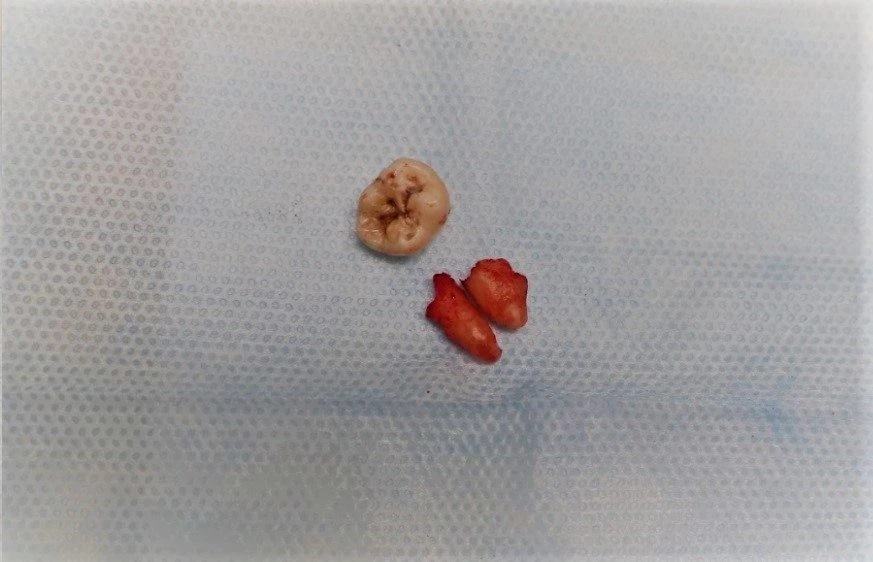

Poniżej przedstawiamy zabieg usunięcia zatrzymanego zęba mądrości wykonany przez specjalistę chirurgii stomatologicznej - dr Tomasza Kozioła, który polegał na znieczuleniu miejscowym, odsłonięciu zęba, zniesieniu blaszek kostnych z okolicy zęba, odcięciu korony i jej usunięciu, rozdzieleniu korzeni i ich usunięciu oraz zszyciu rany.